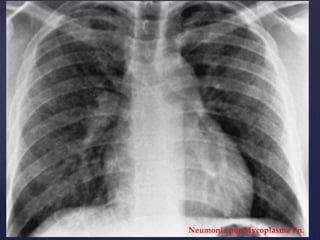

CONFIRMAMOS EL

DIAGNÓSTICO:

RADIOGRAFÍA DE TÓRAX FRENTE Y PERFIL

Neumonía por Chlamydia Pn.